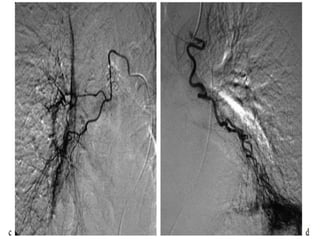

Bronchial artery embolization